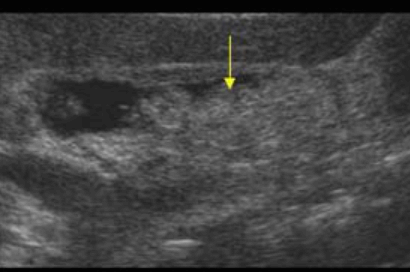

US finding

- 담즙으로부터 침전된 작은 미립자 물질의 혼합물

- 균일한 중간에코로 보이며 후방음향음영이 없다(결석과의 감별)

- 환자체위 변화로 인한 이동성 (용종과의 감별)